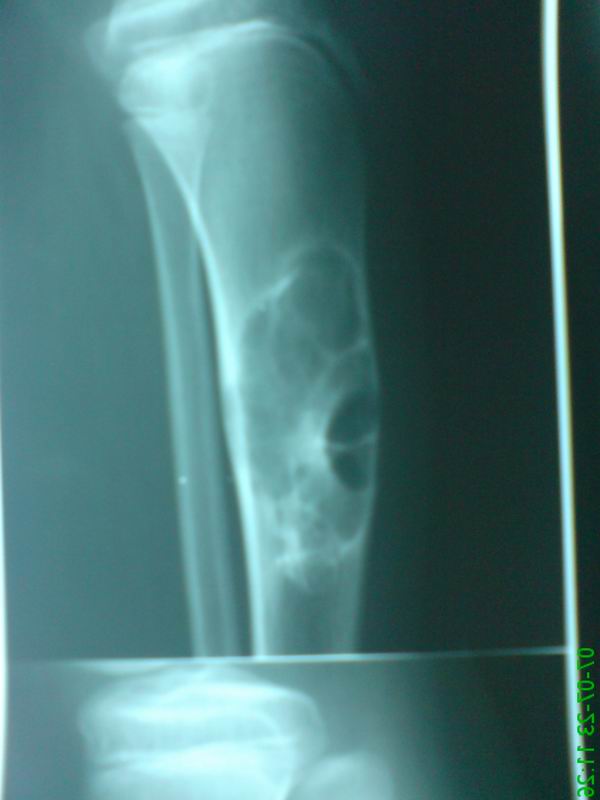

标题: PED0280:女性,10岁,左小腿无诱因疼痛,一般状况良好,无发热乏 [打印本页]

标题: PED0280:女性,10岁,左小腿无诱因疼痛,一般状况良好,无发热乏

胫骨中上段多房囊肿,呈蜂窝状向外膨胀,囊内含有粗细不等的房间隔。考虑动脉瘤样骨囊肿!

胫骨骨干增粗,骨皮质呈膨张性改变。髓腔扩大,其内有多个圆性低密度影,且有长短不一的骨瘠影。邻近骨质硬化。外围骨皮质部分消失。考虑软骨粘液样纤维瘤可能性大。

胫骨中上段多房囊肿,呈蜂窝状向外膨胀,囊内含有粗细不等的房间隔,偏心性生长。考虑良性骨肿瘤----1软骨粘液性纤维瘤。2骨化或非骨化性纤维瘤。

软黏纤>骨化性纤维瘤。髓腔侧硬化明显,边缘扇形,大囊套小囊,皮质偏心膨胀,分隔粗细不等,无明显钙化,首先考虑软黏纤,年龄及病变部位也相符。骨化性纤维瘤可有类似改变,其他不考虑。